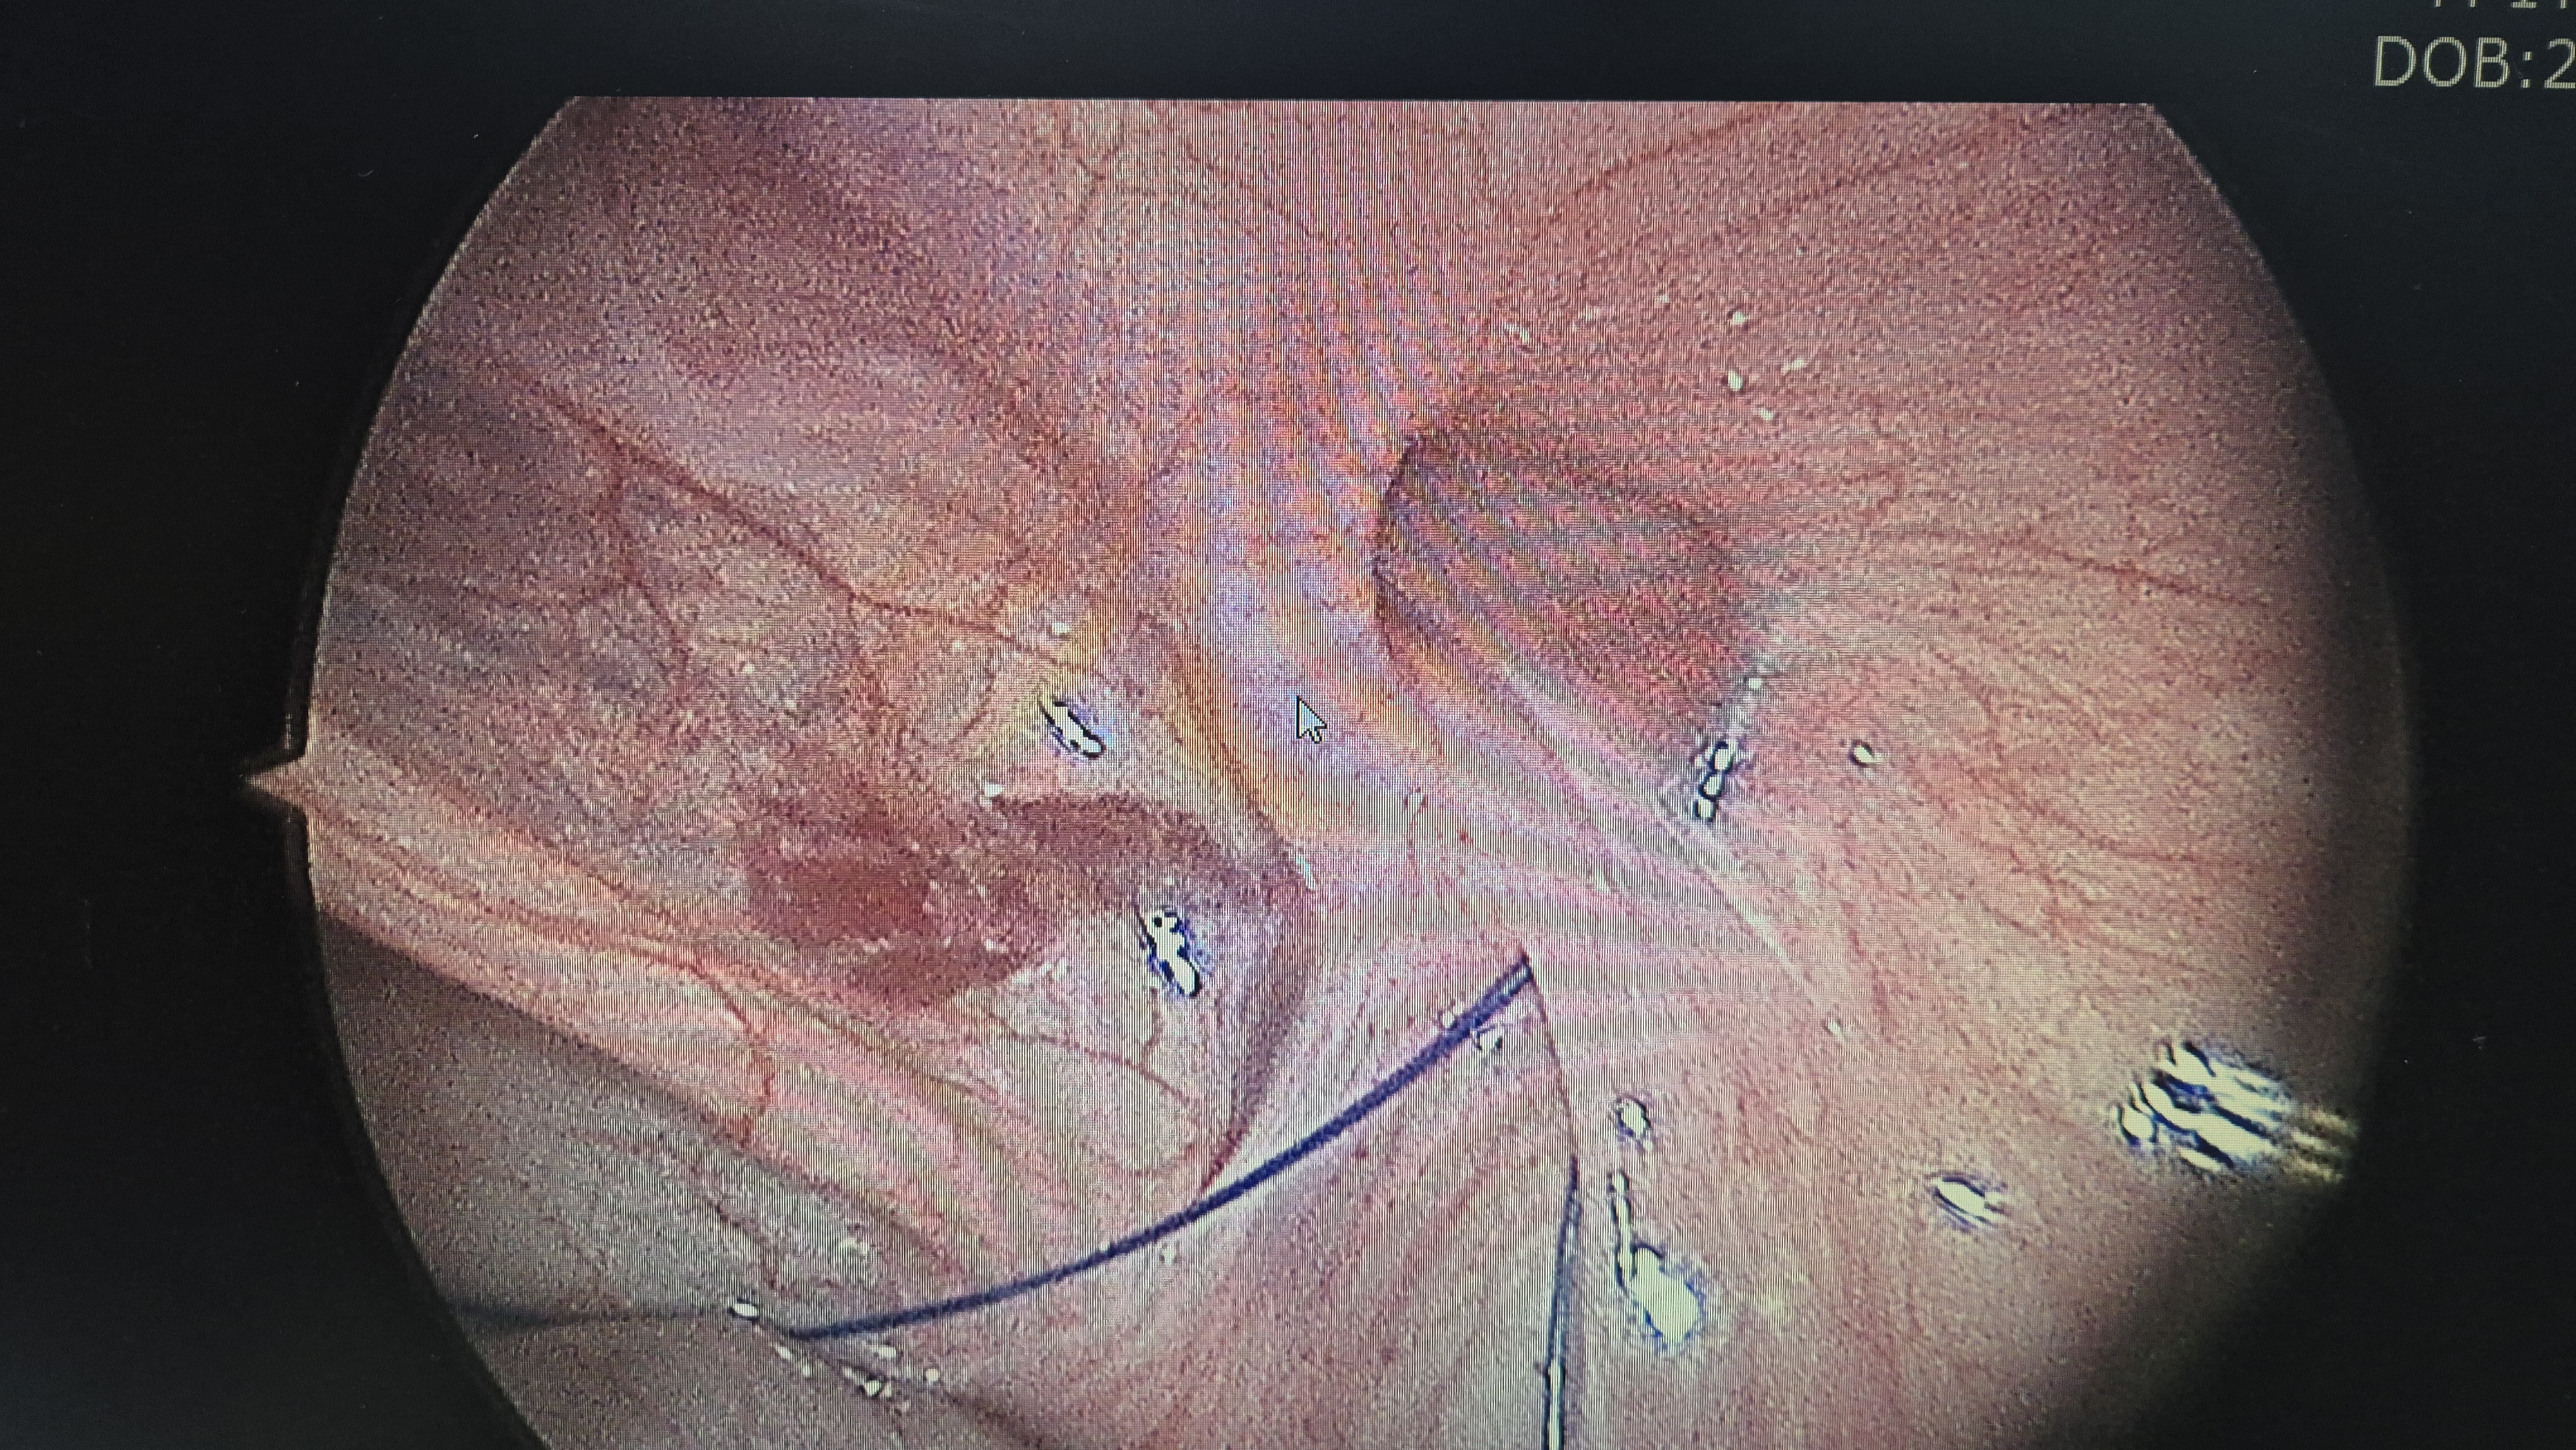

우측 서혜부 탈장.

교정중.